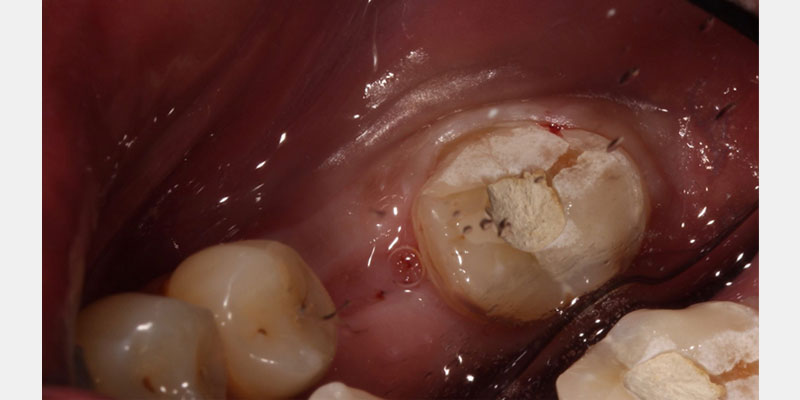

Compromised endodontically treated teeth with minimal tooth structure can be challenging to restore. Traditional approaches of a prefabricated post and core or cast post and core have worked well. However, there are instances where a post and core may be especially difficult or not feasible for a tooth. The endocrown provides an alternate approach for saving and restoring these compromised teeth.

Since the early work on endocrowns was published by Bindl and Mormonn, a host of other studies have looked at preparation design for endocrown restorations. When preparing a tooth for an endocrown, a 2.0 mm occlusal reduction with extension into the pulp chamber is required.

The literature suggests a shoulder and a chamber finish line2, 3, 4 with the extension into the pulp chamber protruding approximately 2.0 mm into the chamber.5 Minimal retention is present, and thus, these restorations must be bonded in place with resin cement.